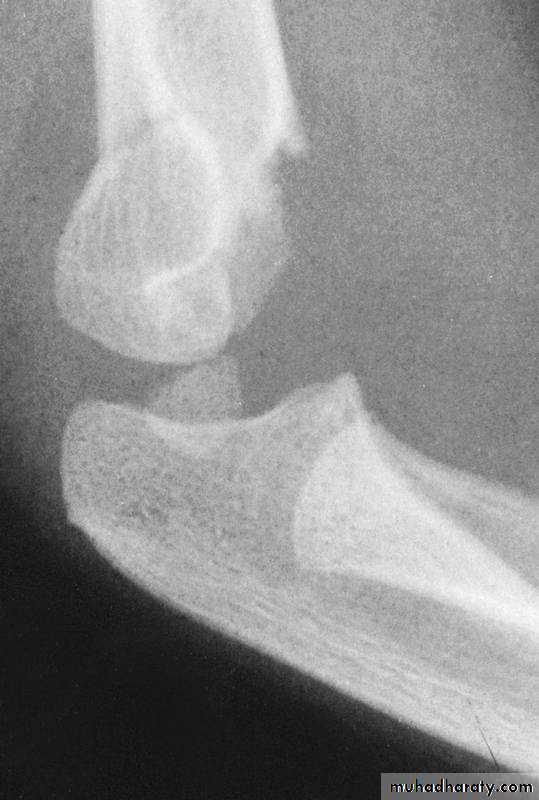

A more careful evaluationof our original “undisplaced” fracture

reveals both deformities were present

on the original x-rays.

Medial greenstick collapse

+Distal hyperextension

The crescent sign

indicates a varus alignment.

The anterior

humeral line

barely passes

through the

capitellum.